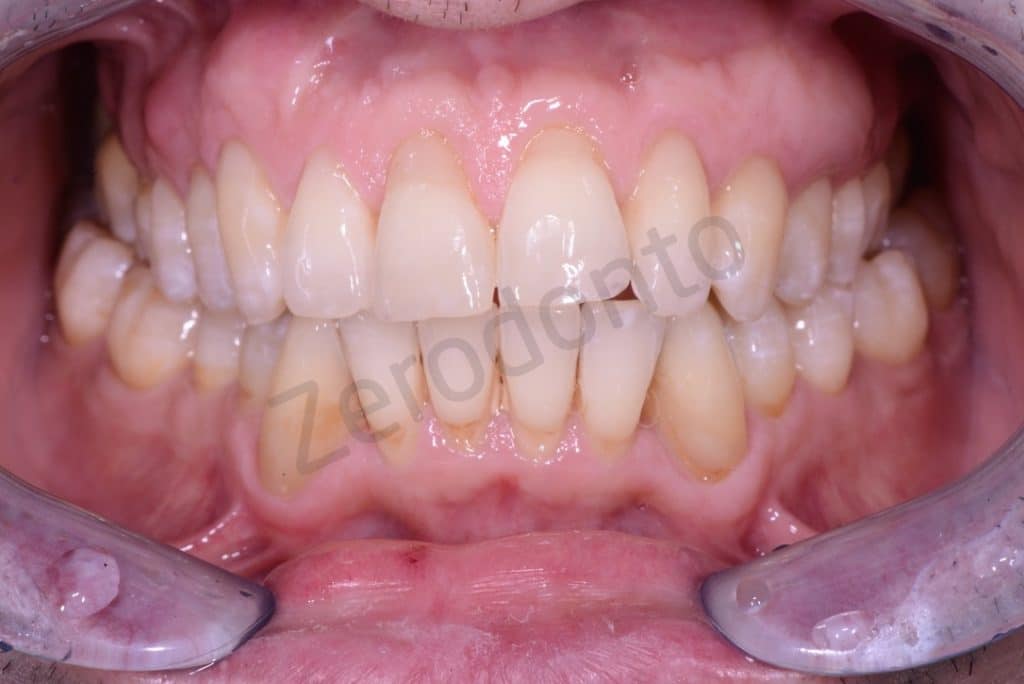

Initial situation

Frontal view